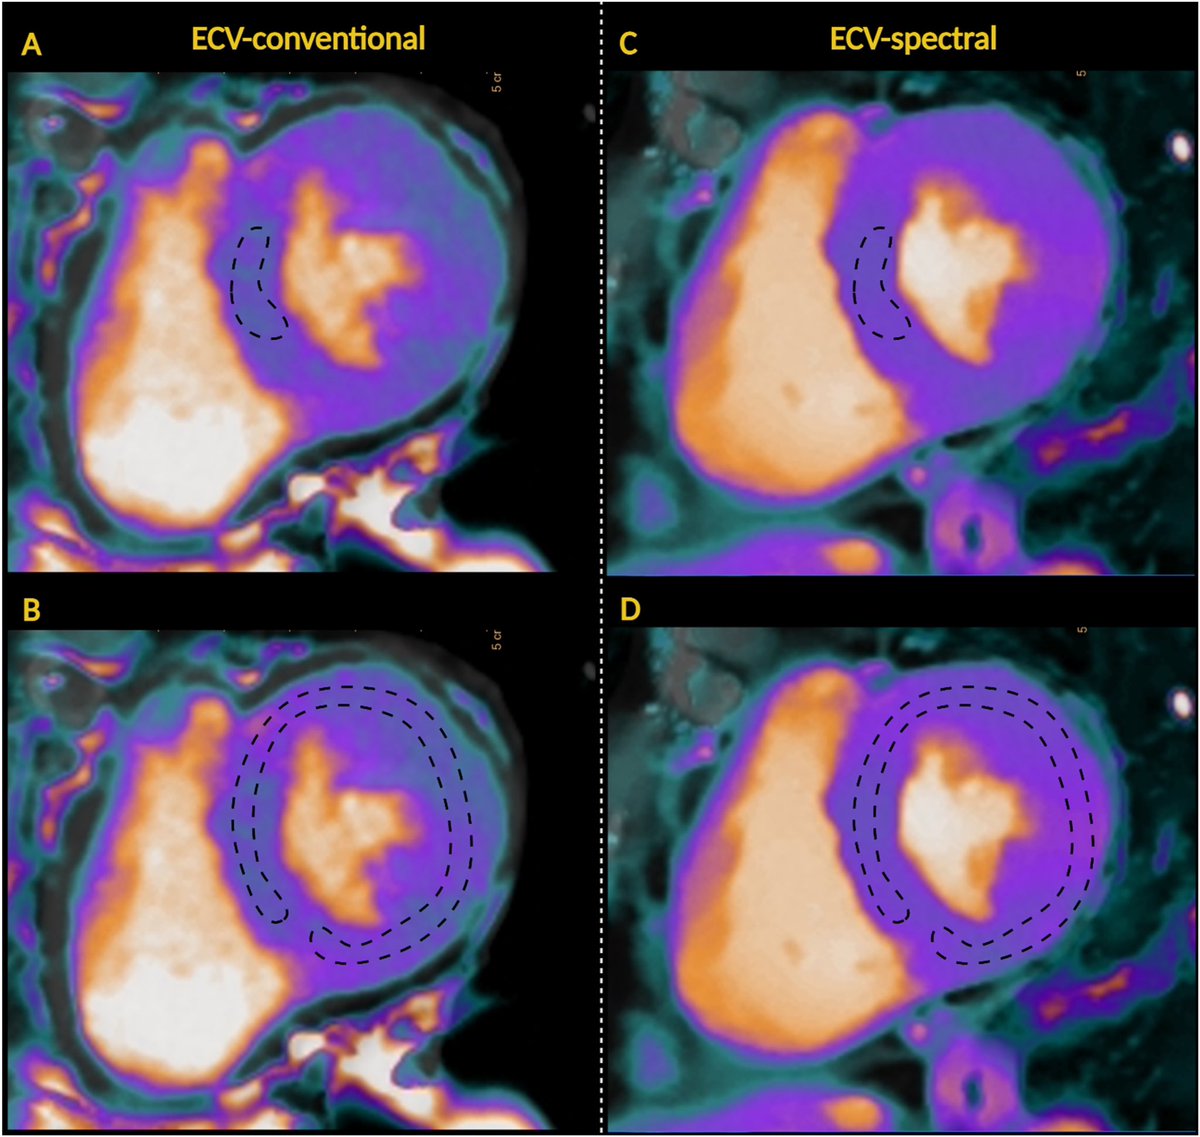

Comparison of dual-energy iodine and standard subtraction methods for myocardial extracellular volume quantification using cardiac computed tomography Daniel Lorenzatti, MD. Annalisa Filtz Pamela Piña S. Jeirym Miranda , MD✨ Felipe Contreras Y. Andrea Scotti João Cavalcante Azeem Latib Journal of Cardiovascular CT